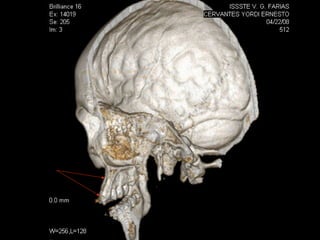

AmeloblastomaAmeloblastoma

Ameloblastoma

Trismus importante debido a queTrismus importante debido a que

El tumor ya rompió el hueso com-El tumor ya rompió el hueso com-

Pacto de la cara interna de laPacto de la cara interna de la

Mandíbula y empezó a tomar elMandíbula y empezó a tomar el

Músculo pterigoideo interno.Músculo pterigoideo interno.

Trismus importante debidoa queTrismus importante debido a que El tumor ya rompió el hueso com-El tumor ya rompió el hueso com- Pacto de la cara interna de laPacto de la cara interna de la Mandíbula y empezó a tomar elMandíbula y empezó a tomar el Músculo pterigoideo interno.Músculo pterigoideo interno.